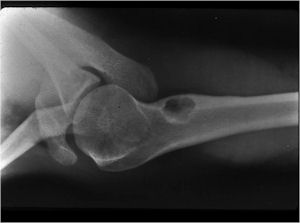

- Geographic, circumscribed lesion usually around 5cm in size.

- There may be expansion of bone, cortical thinning and cortical breakthrough. A soft tissue mass may accompany this lesion but the soft tissue component is usually contained by the periosteum.

- The lesion may be entirely radiolucent but usually shows some degree of mineralization. Mineralization may appear stippled like cartilage but do not see chondroid pathologically. Mineralization is sometimes better detected on a CT scan rather than an x-ray.